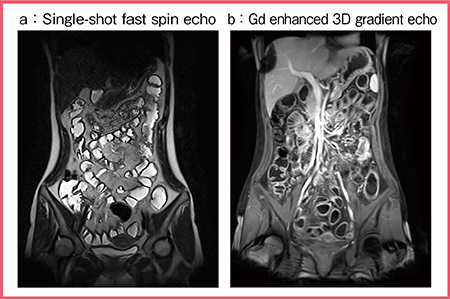

TRILLIUM OVALの特長の一つは,FOV 50cmの広範囲撮像が可能なことである。4ch-4port RF照射システムがRF照射不均一の低減に大きく寄与しており,広範囲を撮像しても均一な信号が得られる(図1)。辺縁には若干,脂肪抑制のムラが生じるが,腸管全体を十分に評価可能である。

図1 FOV 50cmを生かした腸管全体の評価